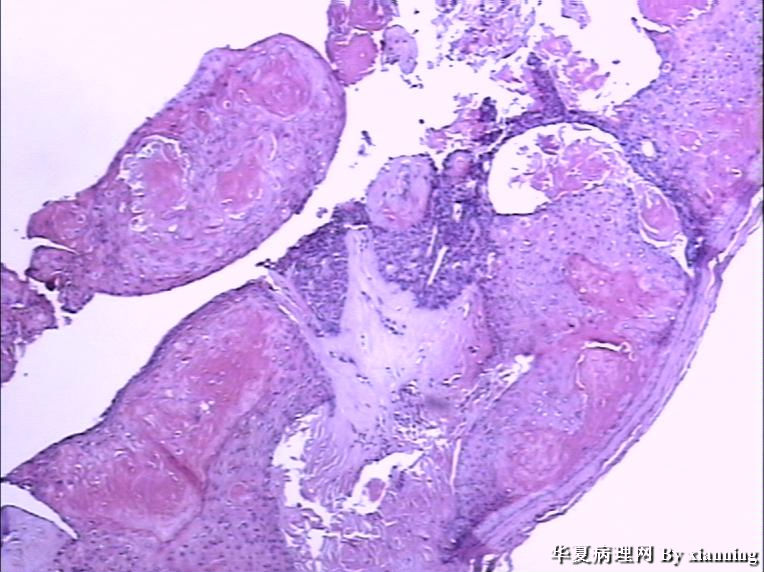

女 50岁 头皮下肿块

巨检:灰白色不规则结节0.9*0.7*0.4cm3,切面灰白色实性质地中等

名称:图4

描述:36580006